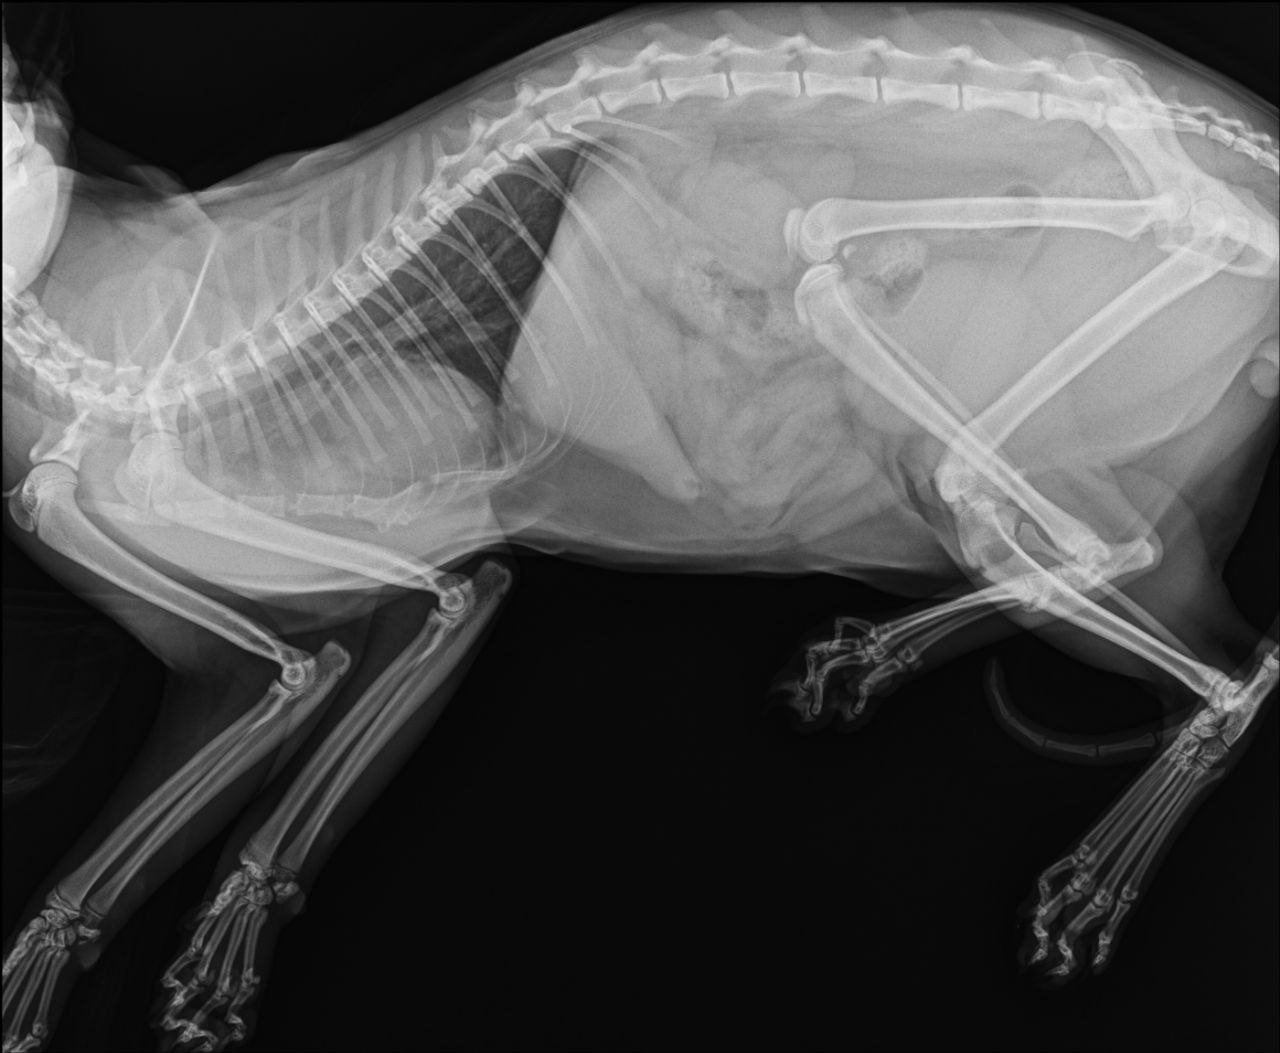

Перелом бедренной кости, требуется операция. В остальном здоров и бодр, ест, пьёт, ходит в туалет.

Тут закрытый перелом не кости а коленного сустава, сильно выраженная бронхиальная картина. Антибиотик нужен

Сёму прооперировали, теперь щеголяет бритой ногой, внутри которой крутые спицы. Отойдя от наркоза, стал бодр и ласков, как всегда, и уже на передержке.